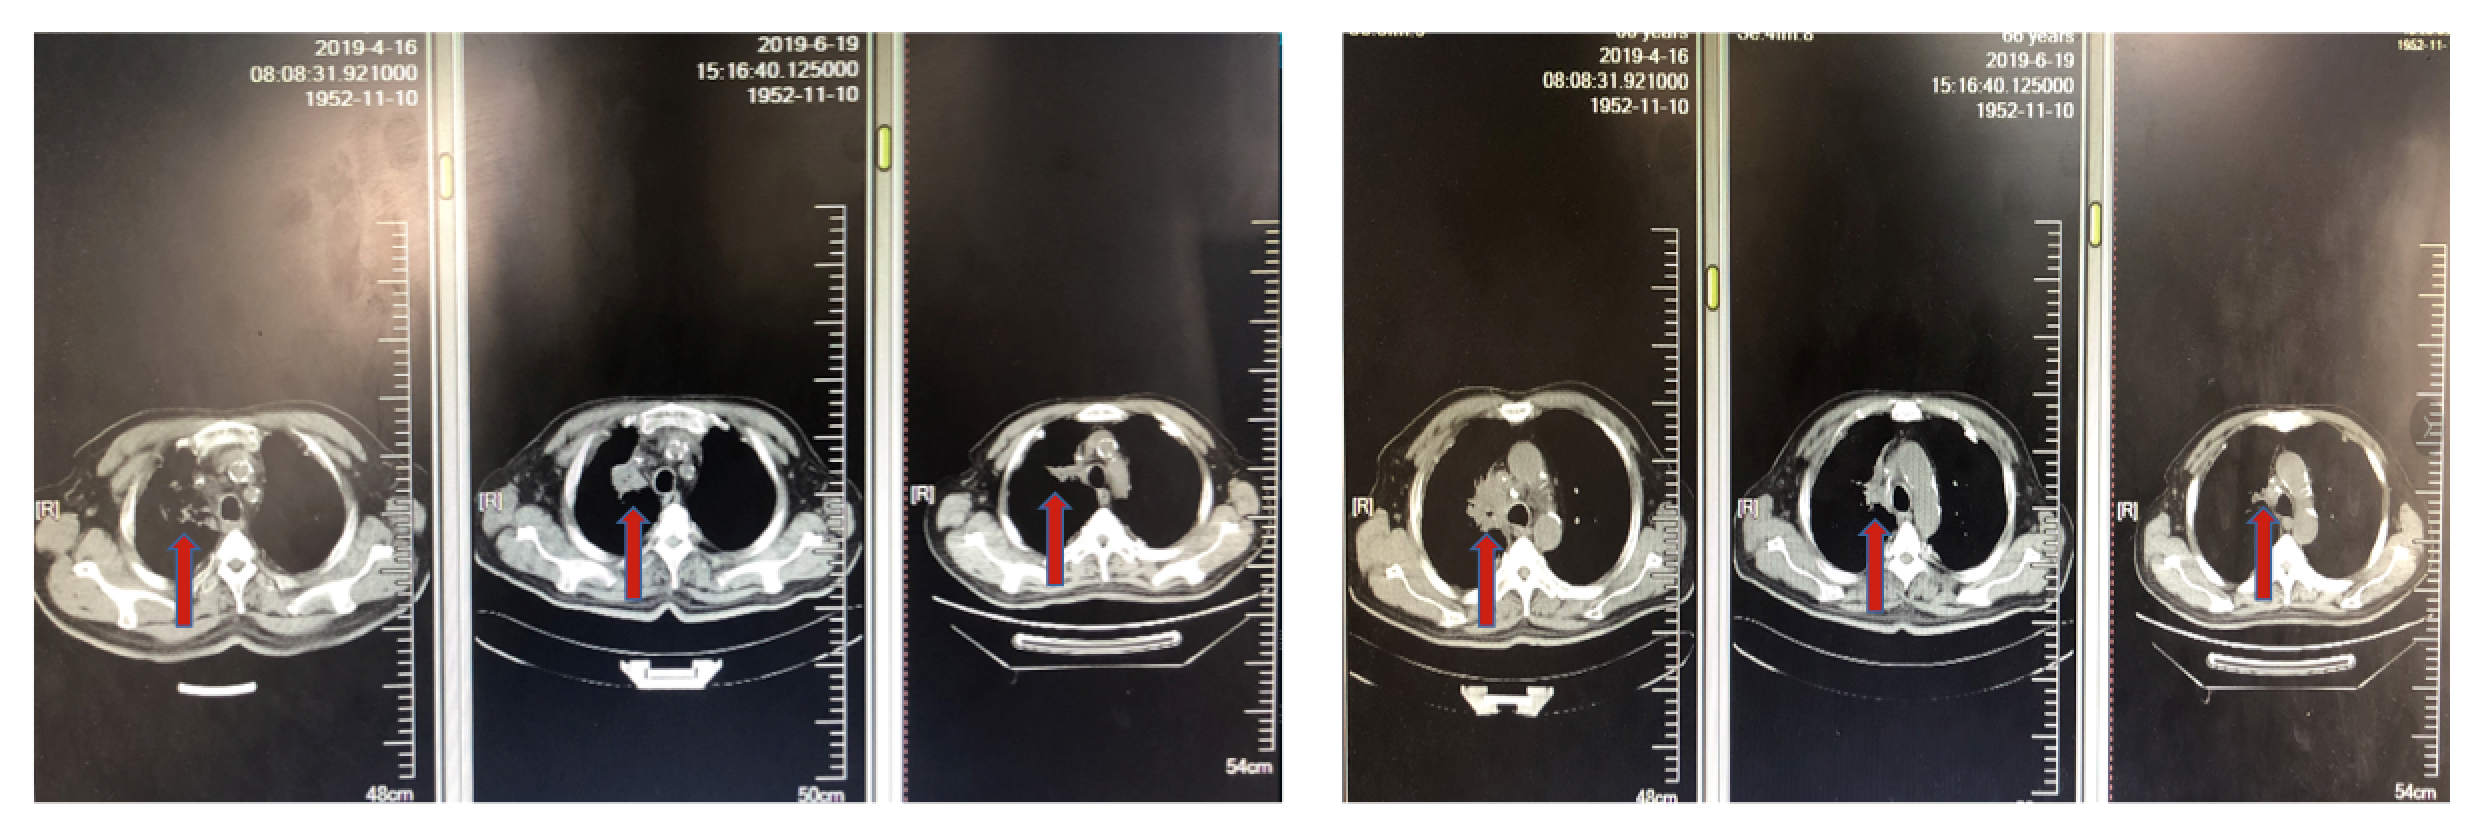

男性,66岁,吸烟30余年。因“咳嗽,咳痰带血1月”入院。既往合并糖尿病史8年,否认肿瘤家族史和其他家族性遗传性疾病史。入院行血常规、生化检查未见明显异常。肿瘤指标示NSE 23.56ng/ml、CA153 34.90U/ml。哈尔滨胸科医院胸部CT示:右肺上叶空洞伴占位性病变;腹部CT检查发现肾上腺结节。支气管镜检查病理示:“鳞状细胞癌”。诊断为:右肺鳞癌,伴纵隔淋巴结转移,右肾上腺转移;糖尿病。

图1. 基线胸部CT检查

图2. 基线腹部CT发现肾上腺转移